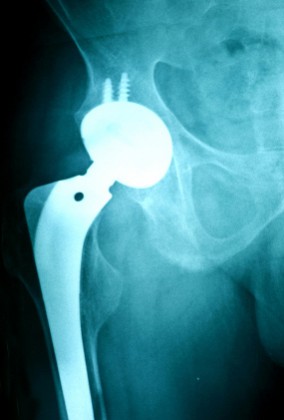

Metal Hip Implant LawsuitBarbara E. and Charles G., a married couple from Pennsylvania, have joined the multidistrict litigation pending over the ASR hip implants produced by Johnson & Johnson’s DePuy unit.

Barbara had a DePuy ASR metal hip implant placed in her right hip in August 2008 and another in her right hip in November 2008. She alleges that these hip implants have resulted in multiple medical complications including synovitis, mechanical failure, metallosis, and the need for revision surgery, as well as pain, emotional consequences, additional medical expenses, loss of earnings, and loss of future earning capacity. At the time she filed her DePuy hip lawsuit, Barbara still had both hip implants in place, but was scheduling to have both of them removed.

DePuy ASR Metal Hip Implants

The ASR hip implant was first sold in the United States in 2005. It was supposed to have a service life of 20 years and offer greater range of motion than other hip implants on the medical device market. However, many of these metal-on-metal hip implants allegedly failed not long after implantation, causing pain and dislocations. Also, the metal-on-metal hip implants reportedly had a tendency to shed chromium and cobalt into the bloodstream, resulting in metallosis in some implant recipients. Some implants had to be surgically removed in order to stave off hip implant side effects, some of which can be permanent.